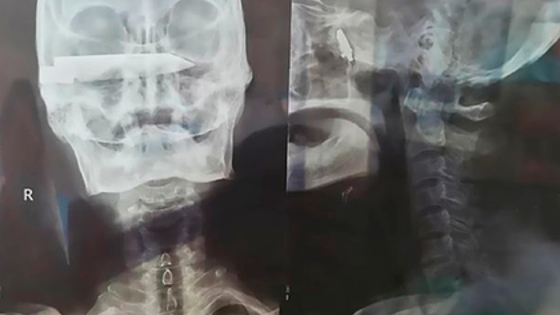

В 2012 году непростым медицинским случаем заинтересовались два приезжих хирурга. При обследовании у больного обнаружили потерю зрения в правом глазу и почти полный паралич конечностей с левой стороны. Медики отвезли фермера в крупную больницу провинции Шаньдун.

Операция, которую проводили в два этапа, была разработана оториноларингологом Ваном Цироном и заместителем главы больницы Ваном Баодуном. Над лечением пациента работала целая команда специалистов, в том числе офтальмолог Дан Гуанфу.

2 апреля в ходе двухчасовой операции хирурги благополучно извлекли из головы пациента лезвие. Спустя шесть дней его вновь положили на операцию, чтобы очистить рану от загрязнения. На данный момент пациент восстанавливается под присмотром врачей и уже может самостоятельно ходить. По словам докторов, у него прошли головные боли, а также вернулось зрение в правом глазу.